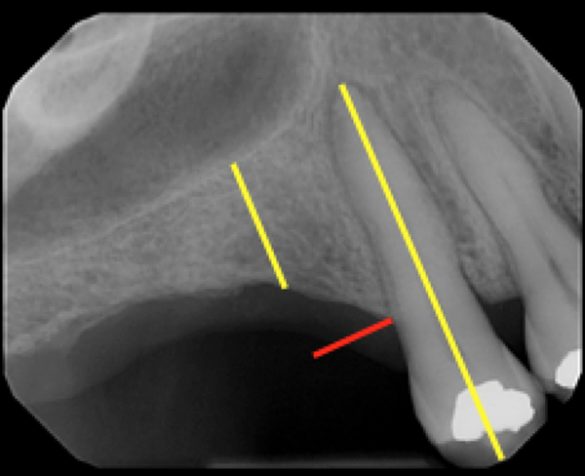

Măsurătorile din scanarea CBCT au fost înregistrate pe secțiunea transversală. O linie dreaptă perpendiculară pe o tangentă la creastă a fost extinsă până la podeaua sinusului maxilar. S-a măsurat lungimea liniei și s-a notat ca „înălțimea crestei CBCT” (fig. 1, 2). Măsurătorile periapicale ale aceleiași zone au fost înregistrate prin extinderea unei linii drepte paralele cu axul lung al dintelui natural sau implantului adiacent, de la creasta alveolară până la podeaua sinusului maxilar. Lungimea liniei a fost măsurată și înregistrată ca „înălțimea crestei PA” (fig. 3).

În trecut, pentru a obține radiografii PA clinicienii foloseau adesea tehnica bisectoare în care raza centrală era direcționată către o linie care bisectează axul lung atât al dintelui cât și al suportului de film. În prezent, este populară tehnica de paralelizare deoarece oferă în mod inerent mai puțină distorsiune și o precizie mai mare în măsurare decât tehnica bisectoare.13 Acest lucru este esențial în special în domeniul endodonției pentru determinarea lungimii rădăcinii. Totuși, această caracteristică nu se aplică în stomatologia implantară, întrucât există o absență a identificatorilor cheie sau a punctelor de măsurare, cum ar fi muchia incizală sau vârful rădăcinii (fig. 4, 5), ceea ce face dificilă măsurarea înălțimii crestei și eliminarea oricărei repetabilități în măsurători, intervenind astfel erori.

În mod similar, atunci când se extrage un dinte, operatorul poate introduce senzorul de raze X în mod eronat și, adesea, dinții restanți și creasta alveolară pot avea un ax longitudinal diferit (fig. 6-8), împiedicând operatorul să atingă adevăratul paralelism pentru o acuratețe a utilizării instrumentului de măsurare.